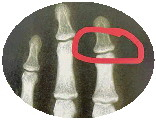

当然,如果想看看孩子的生长发育水平,可定期给孩子测骨龄,即左手或手腕的x光检查,“骨龄的检测建议每半年或一年进行一次”。

李宁说,骨龄是骨骼的年龄,和身高增长密切相关,定期测量有助于预测孩子的生长空间。